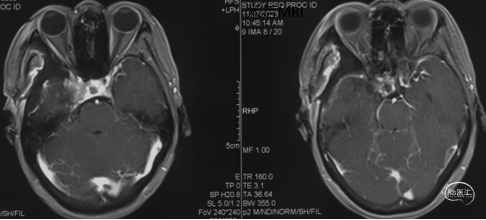

术后复查

术后MRI+增强

显示肿瘤完全切除。